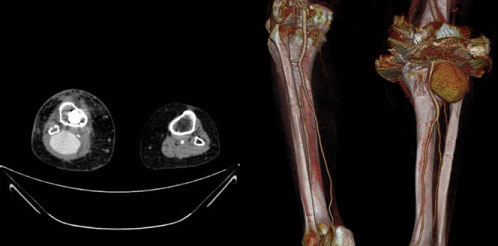

A 76-year-old woman with history of hypertension and right knee osteoarthritis underwent total knee arthroplasty that went without incident. On the seventh postoperative day, she presented edema of the lower limb. Physical examination revealed a pulsatile, painful and progressive growing mass in the popliteal gap, not erythematous and without temperature rise, associated with functional impotence due to compression of the surrounding structures. Distal pulses were palpable and the sensitivity was preserved. Doppler ultrasound was performed on the seventh postoperative day and showed a fusiform dilation of the popliteal artery with turbulent flow inside, suggesting a pseudoaneurysm. She was assessed by Vascular Surgery and was referred to consultations to complete the study on an outpatient basis. She was discharged on the ninth postoperative day. CT angiography on an outpatient basis confirmed the presence of a pseudoaneurysm of 5.5 × 3.8 × 5.9 centimetres in diameter (transverse x anteroposterior x craniocaudal diameters) (Figure 1).

Figure 1: CT angiography image and 3D reconstruction showing the popliteal artery pseudoaneurysm. View Figure 1